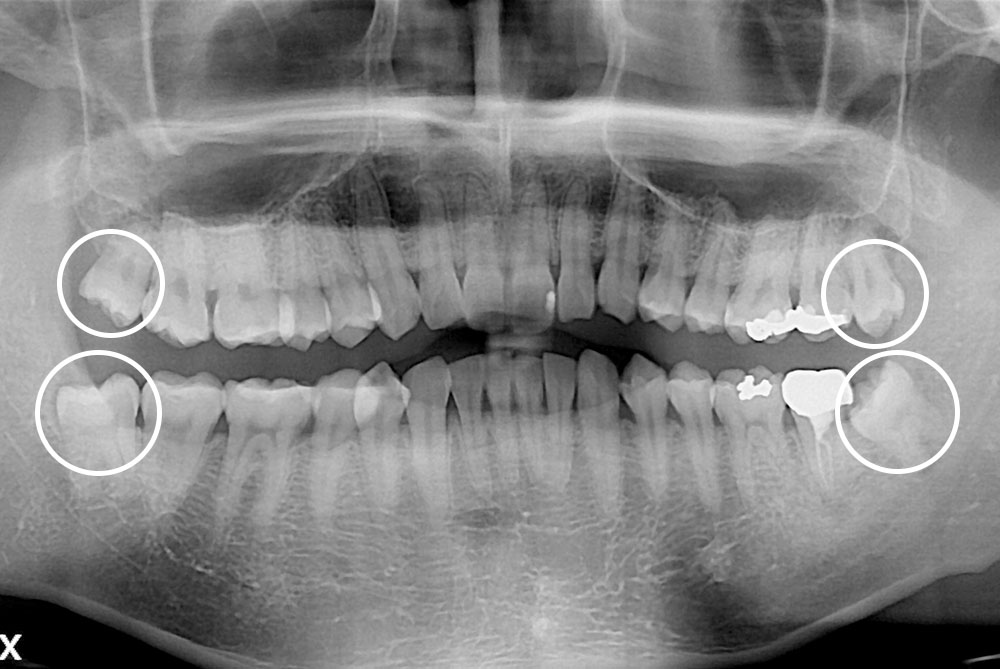

[사랑니] 매복 사랑니 발치

치료후 : 2019-08-19

세종치과는 구강악안면외과학 박사이신 원장님이 발치하는 치과입니다.